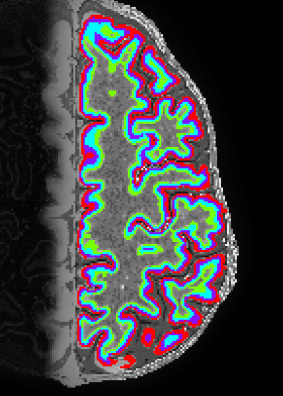

Description: Nighres is a software tool in Python that is built on CBS tools developed by Julia Huntenburg, Christopher Steel and Pierre-Loiuse Bazin. It is specifically designed for high-resolution, layer-dependent MRI analyses.

Advantage: Its open source and very well documented. Its super fast. On my laptop it takes 15 min to get from MP2RAGE data to layers in volume space.

Disadvantage: It is not easily usable on MacOS, just yet. It requires whole brain data for the application of segmentation (it uses whole brain reference atlases). Layering can be done with partial coverage for closed surfaces. Even though it is designed to allow changes made by users, the complicated meta structure of multiple wrappers across multiple programming languages requires advances coding experience.